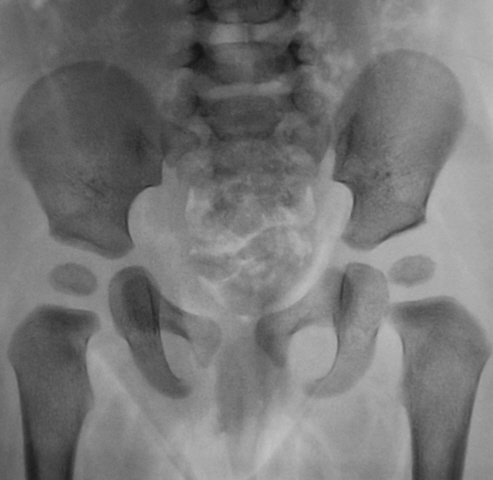

Судя по позвоночнику больная лежит ровно: тогда - наблюдается ассиметрия таза. Головки бедренных костей правильной формы, расположены кнутри от перпендикуляра, опущеннго по краю вертлужной впадины, но головки покрыты не полностью, правая на грани нормы, левая - не совсем. Воображаемые оси бедренных костей центрованы справа - в ср/3 крыши вертлужной впадины, слева - на наружную/3. Линии Кальве и Шентона сохранены. Заключение: Нельзя исключить дисплазии левого тазобедренного сустава. Показана рентгенография с ротацией ступней кнутри (заодно удостоверимся в наличии ассиметрии таза). В дальнейшем у этой пациентки может сформироваться coxa valga, которая может никак себя не проявлять.

Данных за дисплазию нет, развитие тазобедренных суставов по возрасту. Шеечно-диафизарные углы также соответствуют возрастной нароме, предпосылок для вальгизации не вижу.

Центрация оси шейки бедра на тот или иной отдел крыши впадины, несомненно, является наиболее наглядным признаком, на который можно ориентироваться при оценке рентгенограмм тазобедренных суставов. Однако у В.И. Садофьевой (которая и предложила этот метод) в руководстве также указано, что при оценке нужно учитывать, в каком положении находится бедро в момент выполнения рентгенограмм, и при приведении/отведении конечности учитывать эту погрешность. В данном случае можно заметить, что бедро несколько приведено. Соответственно, если провести ось шейки из строго нейтрального положения бедра, то будет видно, что центрация не нарушена.

Если считать положение пациента правильным (ориентируясь по позвоночнику), то асимметричными выглядят крылья подвздошных костей, правое крыло более параллельно плоскости снимка, крестец чуть отклонен влево. Если какая-то клиника есть (а она, наверное, есть, иначе бы не снимали), то, возможно, она вызвана блоком крестцово-подвздошного сочленения, или еще какой-нибудь патологией с его стороны.

Ребенок лежит неровно - разная ширина подвздошных костей, запирательных отверстий, может небольшая дисплазия слева и есть (крыша вертлужной впадины, кажется, несколько скошеной, возможно, за счет укладки), но подвывиха никакого нет.